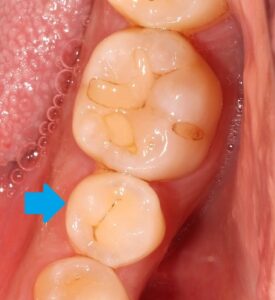

虫歯をすべて取り除き、歯の形を整えます。

虫歯は神経までは達していませんでした。良かったですね。

虫歯の深い箇所はレジンでコーティング保護してあります。

歯の中が綺麗になりましたね!

あとは歯型を取ってセラミックインレー(部分的な詰め物)を製作します。

後日セラミックがセットされた状態です。

どこを治療したか分かりませんね。

綺麗にセラミックがセットされました(^^)/

あの真っ黒な虫歯が、元の歯のように修復されましたね。

セラミックは汚れが付きにくいので再度虫歯になるリスクは低くなります。